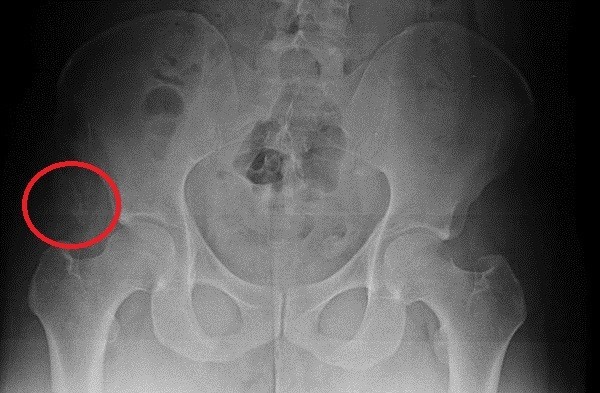

[영상의학 분야 아시아 권위자]로 꼽히는 양승오 박사의 설명이다.▲ 박주신씨의 골반 부위 X-Ray 사진.ⓒ 뉴데일리DB“오른쪽 엉덩이 쪽에서 골절된 뼈 조각을 찾았다.

저는 매일 같이 뼈만 보는 사람이다.

사진을 들여다보고 있으면 어느 정도의 정황을 유추할 수 있다.엑스레이를 보면 청소년기에 근육이 붙는 자리 쪽 오른쪽 골반 뼈에, 견열골절(인대가 손상되면서 뼈조각이 떨어져 나간 것)이 왔다.

이 엑스레이의 주인이 아주 험하게 살았다고 단정하는 이유다.”